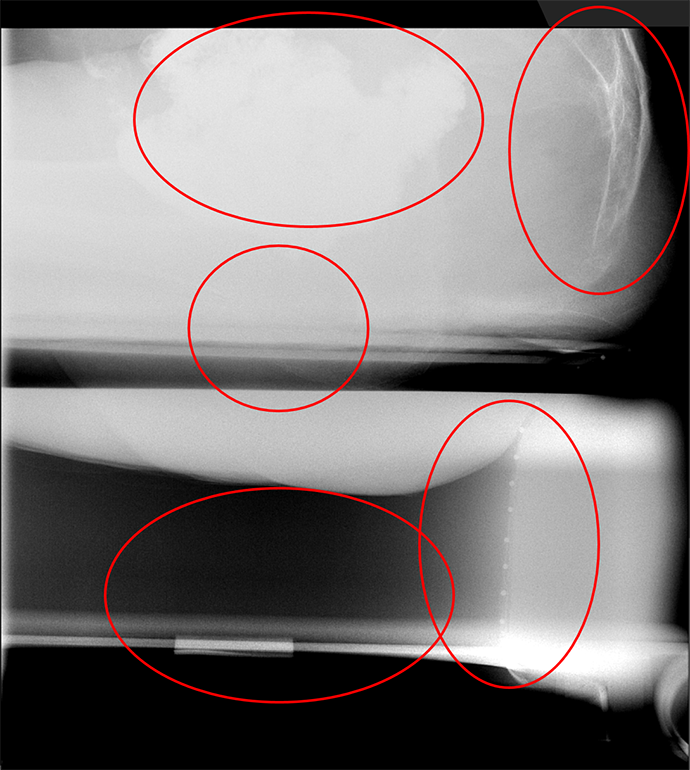

- Obtain spot films while that patient performs the following maneuvers:

- Rest

(key image 2).

- Squeeze

(key image 3).

- This should be done with maximum voluntary contraction of the sphincter and pelvic floor muscles.

- Ask the patient to try and use their muscles as if they were trying to hold in a bowel movement.